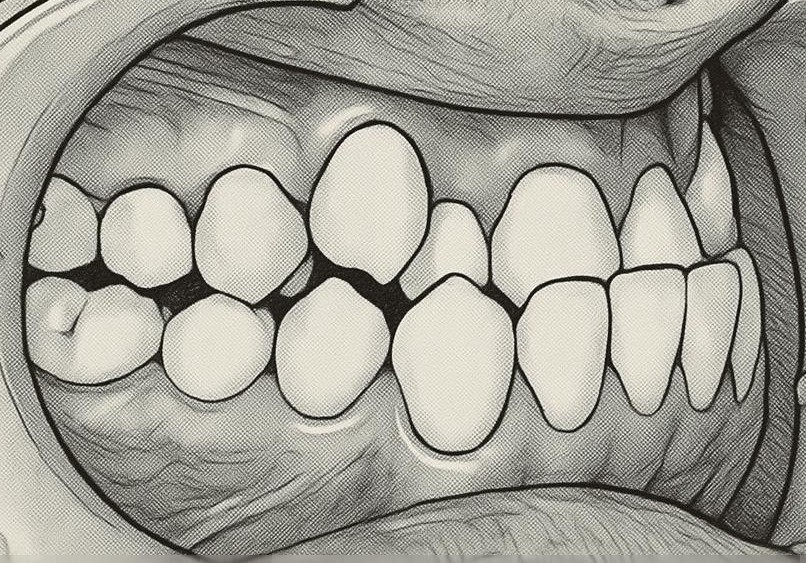

不正咬合の種類:叢生

叢生

※これは顎が小さいために歯の生えるスペースがないために起こることです。

歯が大きかったりあごが小さかったりして両者のバランスが悪い人では、前歯のでこぼこが見られます。